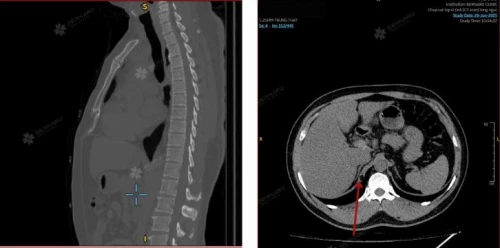

Vừa qua, Bernard Healthcare đã tiếp nhận khách hàng nam V.P.C. (51 tuổi). Kết quả CT Scan lồng ngực ghi nhận tổn thương: Lipoma chân hoành - một khối u mỡ lành tính nằm tại chân cơ hoành, vị trí nối cơ hoành với cột sống. Đây là loại tổn thương mỡ khá phổ biến ở những vùng khác, nhưng ở vùng chân hoành là cực kỳ hiếm gặp. Ở hiện tại, khối lipoma chưa gây ảnh hưởng đáng kể đến chức năng hô hấp hay tiêu hóa. Tuy nhiên, để phòng ngừa các biến chứng do u tăng kích thước hoặc tiến triển, bệnh nhân được tư vấn thay đổi lối sống, theo dõi triệu chứng kỹ lưỡng và lên kế hoạch tái khám sau 6 tháng.

Trên phim chụp MRI hay CT Scan, khối u mỡ ở vị trí này đôi khi bị nhầm với thoát vị cơ hoành, u vùng ngực - bụng trên hoặc các tổn thương khác. Nếu không sử dụng đầy đủ các kỹ thuật chẩn đoán hình ảnh phù hợp, bản chất lành tính của khối u có thể không được nhận diện ngay từ đầu.

Trong phần lớn trường hợp, CT Scan hoặc MRI chất lượng cao đã đủ để xác định bản chất tổn thương, không cần thực hiện thêm các thủ thuật xâm lấn.